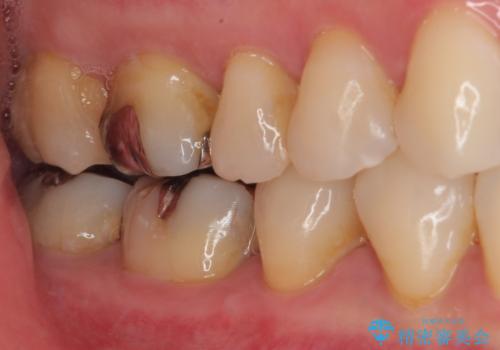

- 当院で矯正終了後に銀歯をやり替えたいとのことで来院された患者様です。

右上の6番目の歯はメタルインレーが大きかったためルジルコニアクラウン、右上の7番目の歯は一番奥で審美的な要素よりも機能面を重視してゴールドインレー修復による治療計画を立案しました。

拡大鏡視野下で保険のプラスチック(コンポジットレジン)、虫歯を除去し、フルジルコニアクラウン、ゴールドインレーに適した形にしました。